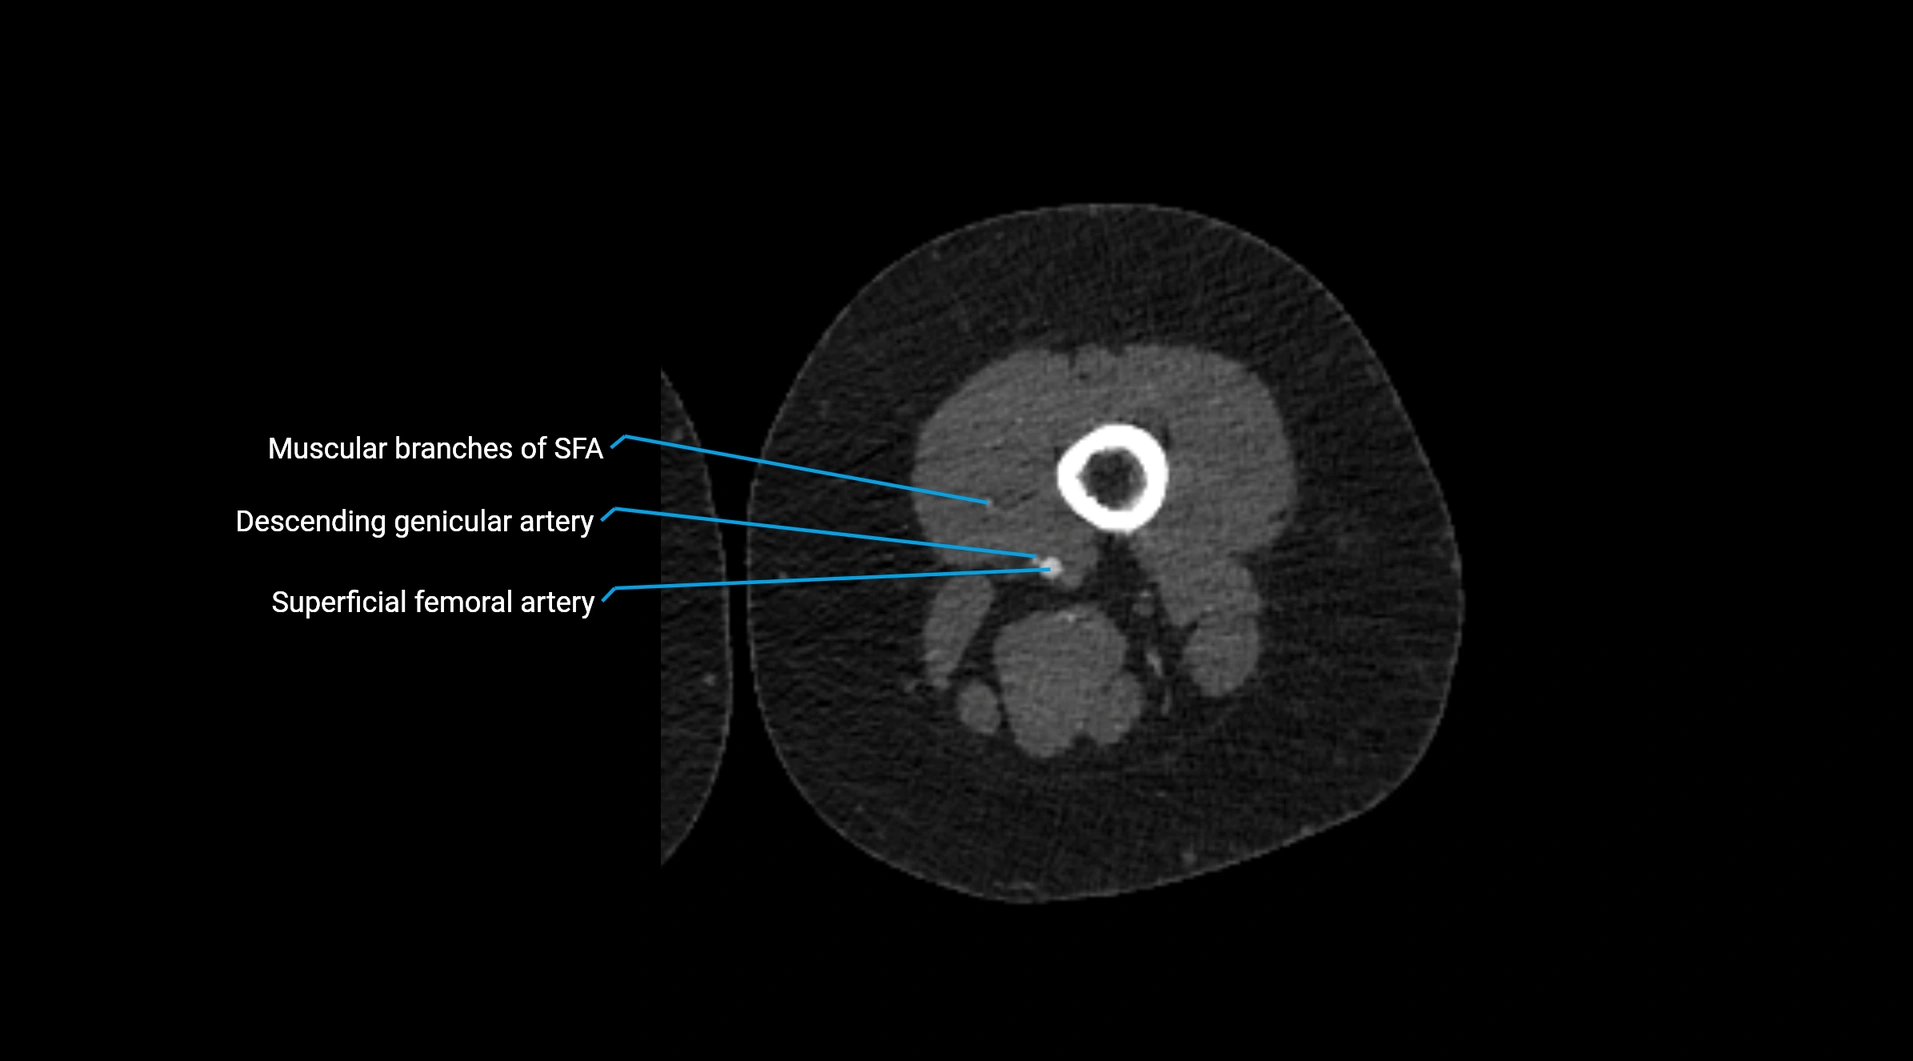

Contrast-enhanced CT (CTA):

• Gold standard for abdominal aortic imaging

• Provides excellent detail of lumen, wall, aneurysm, thrombus, and branch vessels

• Multiplanar and 3D reconstructions help in aneurysm measurement, stent graft planning, and dissection evaluation

• Detects acute rupture, traumatic injury, or occlusion with high sensitivity